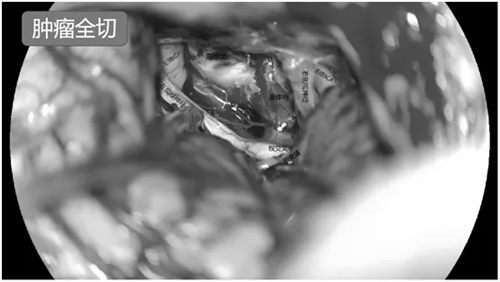

马建主任和周少龙副主任术前详细阅片并在脑海中反复预演手术过程,制定了周密的手术方案,经过2小时精细操作,成功实现肿瘤全切,所有关键神经血管结构毫发无损。术后患者左侧视力得以保留,头痛症状消失,无尿崩、眼球运动障碍等并发症,在鲁小丽护士长带领的护理团队的精心护理下恢复良好,目前已顺利康复出院。

手术在神经电生理科孙楹老师的实时监测下进行,术中肿瘤与周边神经血管,尤其是岩静脉粘连紧密,仅历时1个半小时,即实现全切肿瘤,术后患者耳鸣消失,听力正常,无面瘫、面部麻木等不良反应。